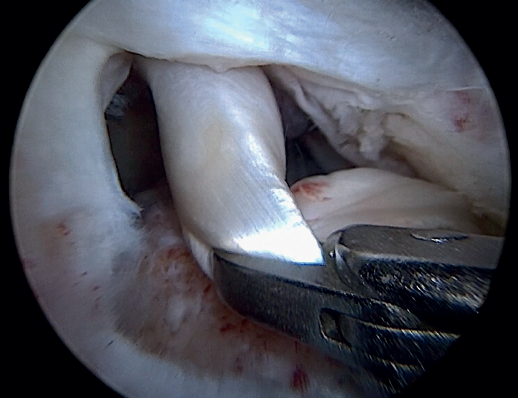

Previously, at intra-articular level, we assessed the quality of the LPB and its insertion in the supraglenoid tuberosity; from subacromial, having prepared the bony footprint on the greater tuberosity, we proceed to release the proximal portion of the tendon from the bicipital groove. The upper part of the transverse humeral ligament is sectioned to mobilize the LPB without damaging it (Figure 2). At this time, the mobility and integrity of the LPB is checked with tendon pulling forceps (Figure 3).